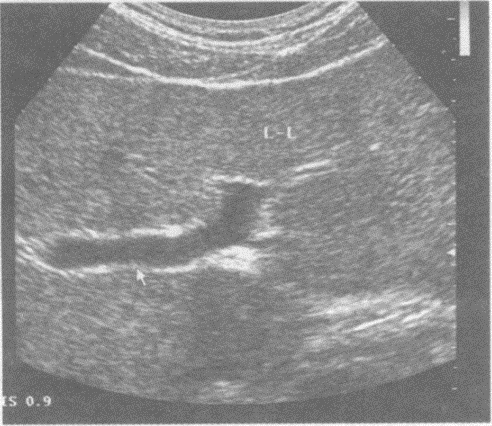

14、单项选择题

请回答下图及彩图中箭头所指部位的解剖名称()。